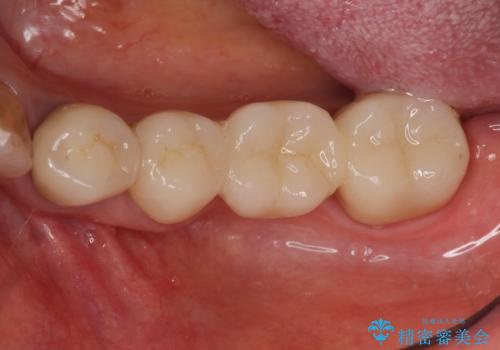

- 46万円(仮歯・ファイバーコア・ジルコニアクラウン×4)費用は治療当時の料金となります

口腔内に金属色でないブリッジが入り、口を開けて笑うことがはずかしくなくなっと喜んでいただきました。